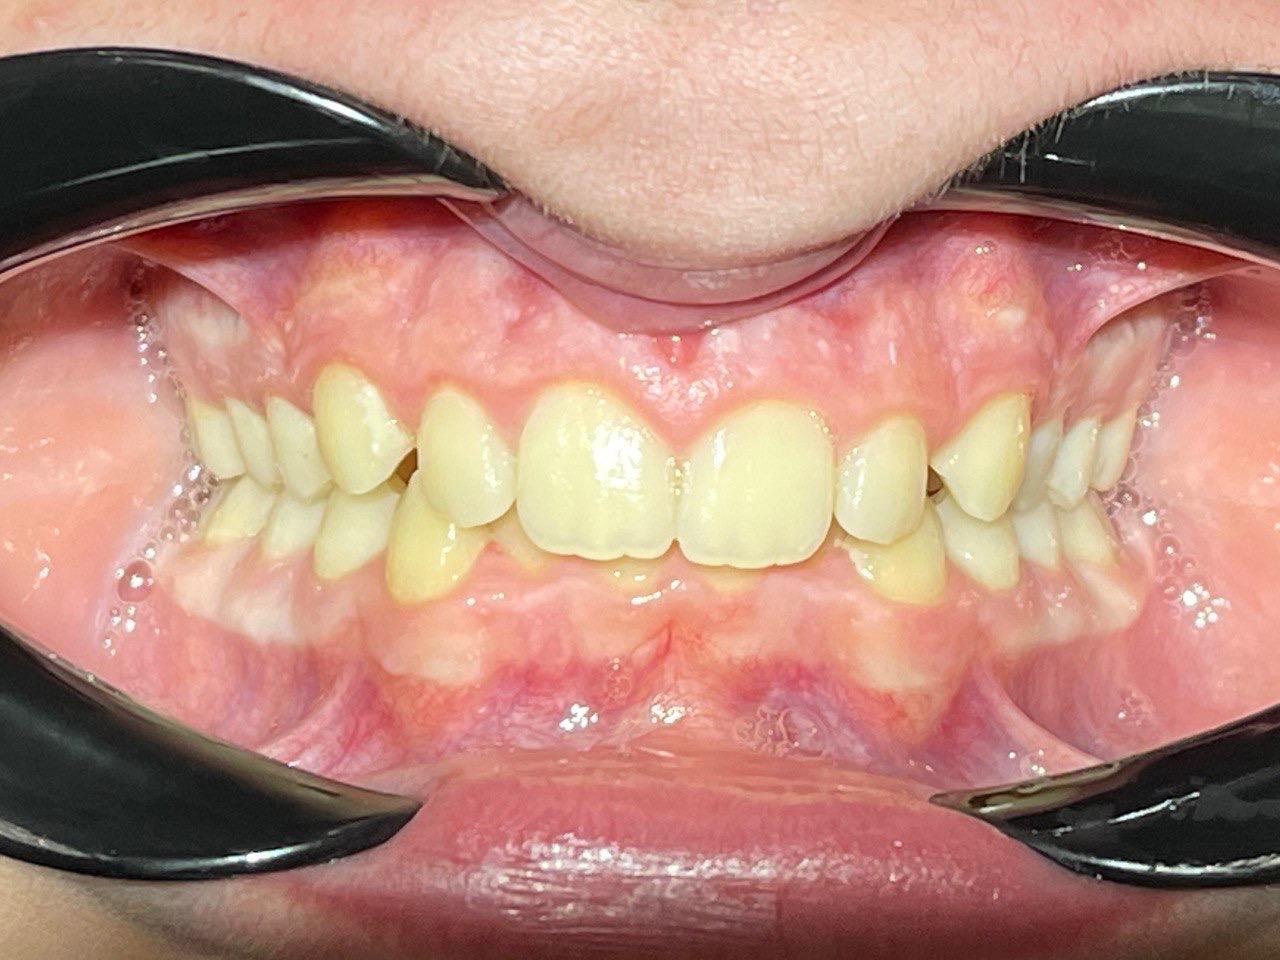

Выявленные проблемы

• Дистальная окклюзия

• Дефицит апикального базиса

• Сужение зубных рядов

• Вестибулярное положение клыков

• Скученность во фронтальных и боковых отделах

Брекет-система Pro